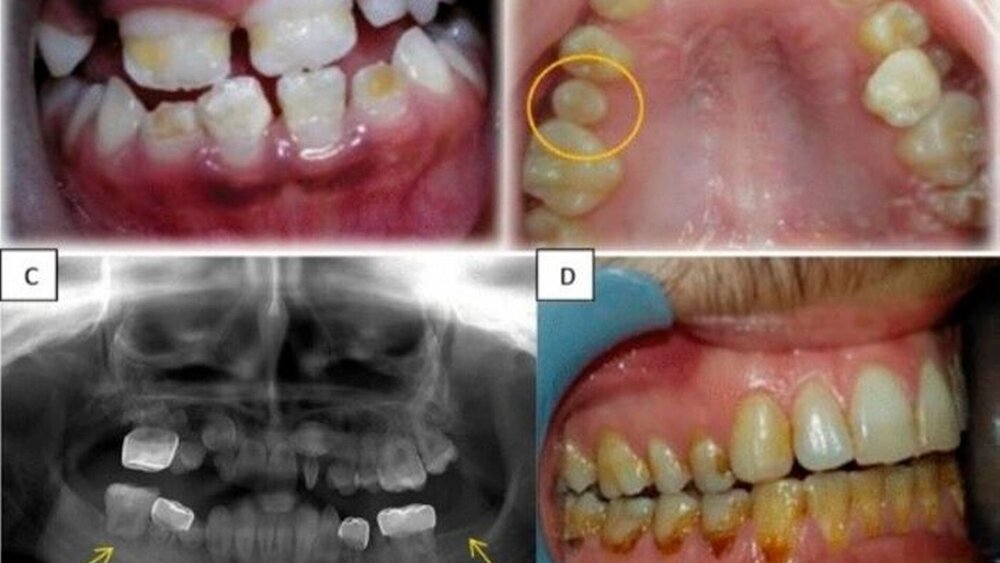

Der Studie zufolge sind die ersten Anzeichen von Zahnstörungen frühestens zwei Jahre nach der Krebsbehandlung zu erwarten. Zu den dokumentierten Anomalien gehörten Hypomineralisierung, Hypoplasie, Mikrodontie und Hypodontie. Zahnwurzelanomalien waren die am häufigsten auftretende Veränderung.

Darüber hinaus gab es auch Fälle von übermäßiger Retention von Milchzähnen, Impaktion, vorzeitigem Durchbruch, verminderter Beweglichkeit des Kiefergelenks, Kieferklemme und Gesichtsdeformitäten. Die signifikantesten geschlechtsspezifischen Unterschiede bei den Zahnanomalien war eine höhere Inzidenz von Mikrodontie bei den Mädchen und eine höhere Prävalenz kariöser Zähne bei den Jungen.